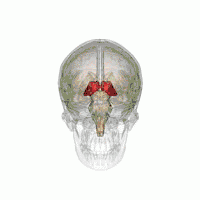

Тала́мус, иногда — зри́тельные бугры (лат. thalamus; от др.-греч. θάλαμος «комната, камера, отсек») — отдел головного мозга, представляющий собой большую массу серого вещества, расположенную в верхней части таламической области промежуточного мозга хордовых животных, в том числе и человека. Впервые описан древнеримским врачом и анатомом Галеном. Таламус — это парная структура, состоящая из двух половинок, симметричных относительно межполушарной плоскости. Таламус находится глубже структур большого мозга, в частности коры или плаща. Под таламусом расположены структуры среднего мозга. Срединная (медиальная) поверхность обеих половинок таламуса одновременно является верхней боковой стенкой третьего желудочка головного мозга[2][3][4].

![]() Таламус в передне-боковой проекции | |